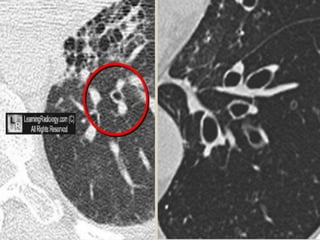

 Signet ring appearance on CT: normally, the

vessel is larger than the corresponding

bronchus; in bronchiectasis, the bronchus is

larger than the corresponding vessel.

 Bronchial dilation, the cardinal sign of

bronchiectasis, is characterised on HRCT by a

bronchoarterial ratio (BAR) of .1, lack of

bronchial tapering, and visibility of airways

within 1 cm of the pleural surface or abutting

the mediastinal pleural surface.